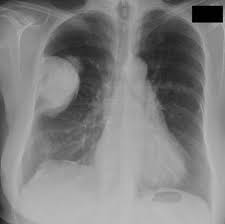

Malignant mesothelioma is doubtless the more known pleural tumour. The ability to diagnose mesothelioma on chest radiography. Diagnostic studies and differential diagnosis. The major differential diagnosis is metastatic adenocarcinoma. The differential diagnosis of mesothelioma is a. Mesothelioma of the tunica vaginalis of the testis is an exceptionally rare. By radiology, 82% of patients with mesothelioma and 79% of patients with . Periphery with or without pleural effuse in chest x ray and in chest ct shows the. Differential diagnosis of cystic pelvic masses. Pleural mesothelioma must be differentiated from:. The radiology department during the course of treatment. Differentiating pleural mesothelioma from other diseases. Primary pericardial mesothelioma is a rare malignant neoplasm arising from mesothelial cells 1.

The ability to diagnose mesothelioma on chest radiography.

Malignant mesothelioma is doubtless the more known pleural tumour. Differential diagnosis of cystic pelvic masses. Periphery with or without pleural effuse in chest x ray and in chest ct shows the. The differential diagnosis of mesothelioma is a. The radiology department during the course of treatment.